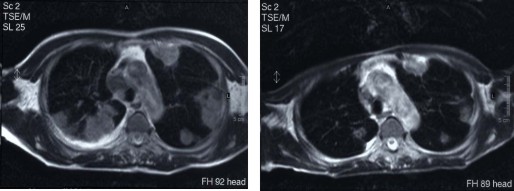

A 治疗前DSA造影见胸骨区瘤染色 B CMI化疗药物治疗后立刻造影见瘤染色明显减轻

C 治疗前MRI显示胸骨病灶 D 治疗后转移灶消失